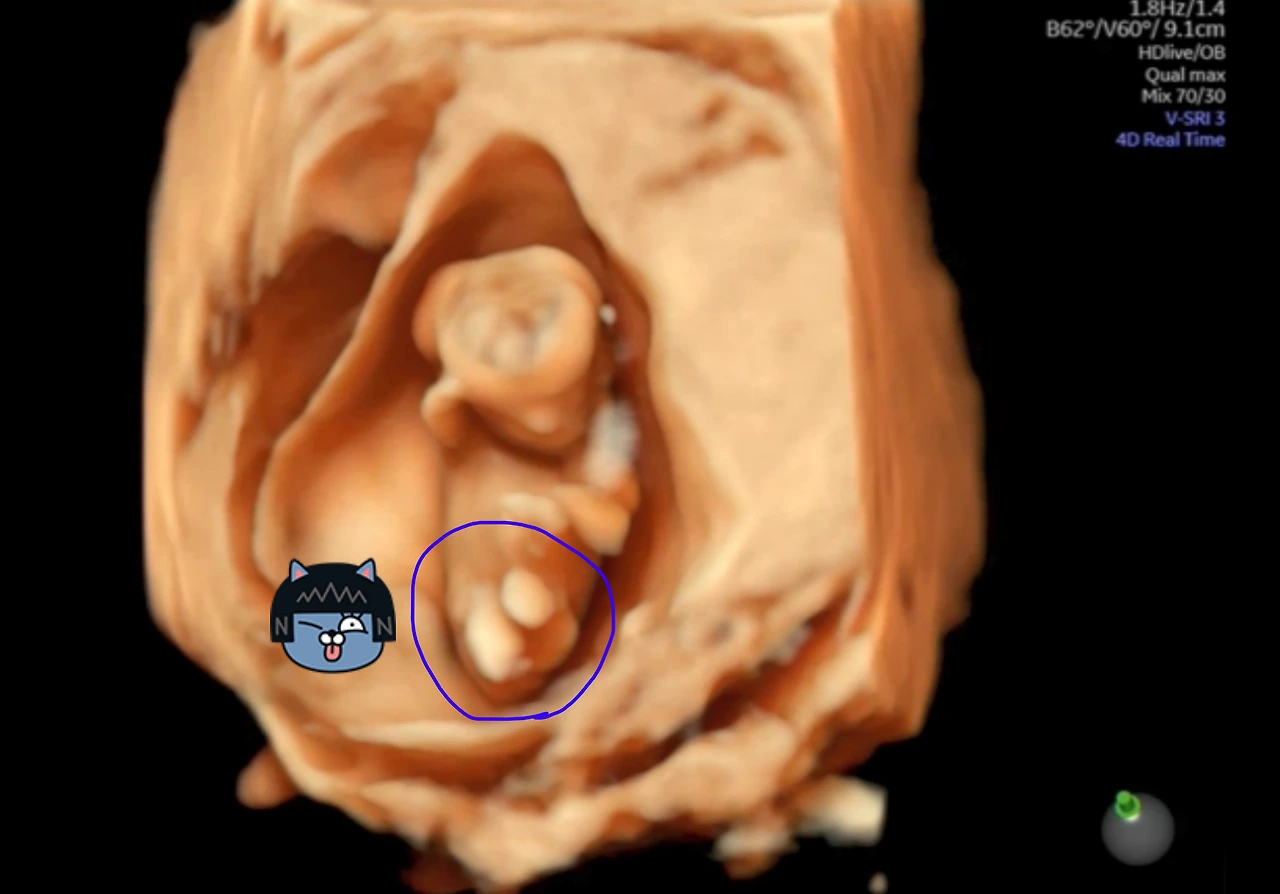

이번에 전원한 산부인과 전문병원은 좋은 장비가 많은데, 그중 하나가 '입체초음파'라고 하네요.

저도 평면초음파 사진만 보다가 입체 사진을 보니 확실히 '팡팡이'가 더 실감이 나는 듯합니다.

그리고 입체초음파 사진을 통해서 성별 구분도 가능하다고 합니다.

보통 12주에 성별을 많이들 확인하기 때문에 '12주 각도법'이라고도 불리는 초음파 성별 확인방법은, 아쉽게(?)도 '팡팡이'가 다리를 꼬고 있어서 확인이 안 되었다고 하네요.

12주 입체 초음파(다리꼬기).PNG